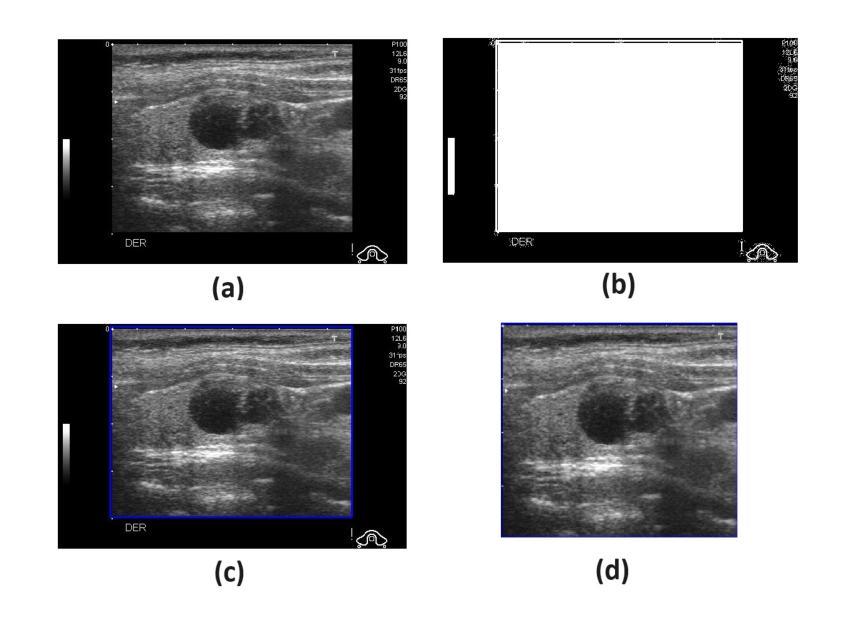

医学影像/Breast Ultrasound 医学影像/Breast Ultrasound

医学影像/Breast Ultrasound 方向最新论文已更新,请持续关注 Update in 2025-09-24 Accurate Thyroid Cancer Classification using a Novel Binary Pattern Driven Local Discrete Cosine Transform Descriptor